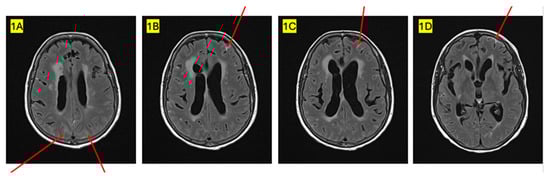

| 2023 (July) | 2023 (December) | 2024 (March) |

| New liver metastasis and significant increase in retroperitoneal disease | Leptomeningeal metastasis causing hydrocephalus | Disease progression and worsening Neurologic symptoms |

| Weekly paclitaxel | T-DXd | No further therapy |